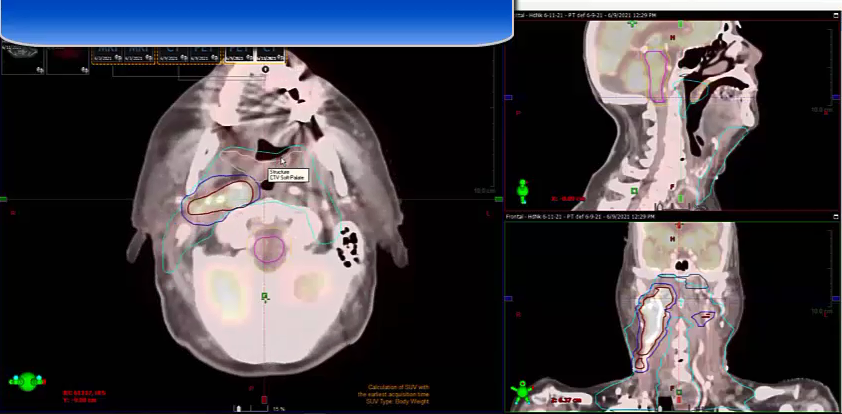

10/31/2022 - Dr. David Sher - Radiation Oncology - US Head & Neck

keep esophagus off 2 cm, 4-5 field VMAT, push a lot harder, omit level 6, PTV, 15 Gy, bilateral tongue, node positive, post-op tonsil, 60 Gy margins, negative margins, chemoradiation, ipsilateral neck, cisplatin, T2N2, tonsillectomy, left neck dissection, SCC, CTV, uvula, soft palate